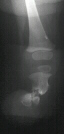

Soon after birth the infant was noted to have a severe deformity

involving the right leg and right foot. Examination of the right

lower extremity demonstrates shortening of the right thigh with

a 10 degree flexion contracture present in the knee. The knee

is noted to be in valgus. The foot is held in a position of severe

equinovalgus with absence of the lateral two rays. The patient

initially underwent a corrective tibial osteotomy and Boyd amputation

of right foot. The postoperative course was complicated by the

development of a nonunion at the osteotomy site.